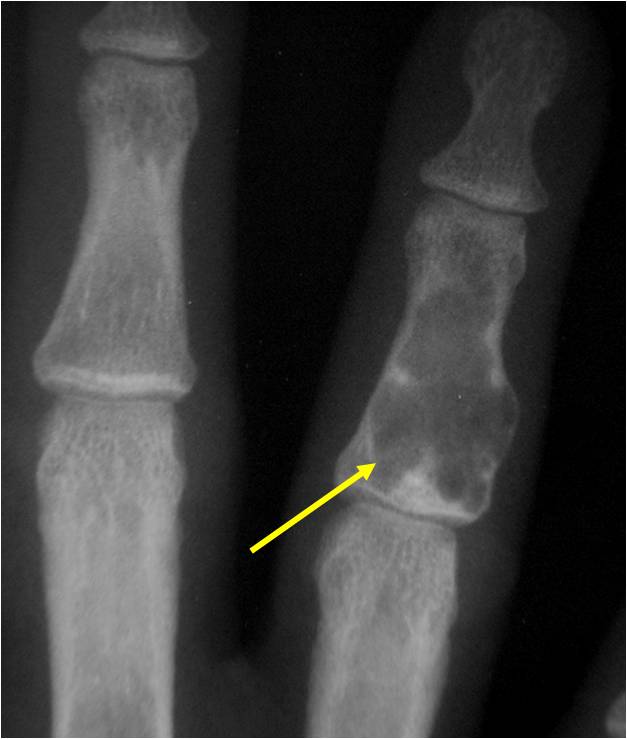

- Cortex may be scalloped and thinned in the phalanges

- Geographic lytic lesion

- Expansile remodeling with thinned cortex

- Chondroid matrix with calcifications in majority of tumors

- There should never be any cortical destruction nor a soft tissue component. If this exists then the tumor must be a chondrosarcoma.

- Endosteal scalloping and cortical expansion is acceptable for phalangeal tumors. In most benign long bone cartilage tumors there is minimal endosteal scalloping but there should be no cortical expansion nor thickening. There should be no cortical destruction and no soft tissue component associated with an enchondroma. Cortical destruction, periosteal thickening, cortical expansion and a soft tissue component indicates a chondrosarcoma of the long bone.